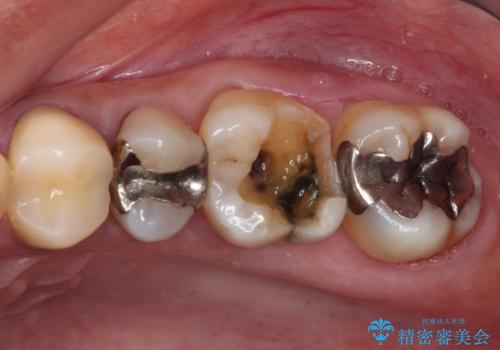

- 奥歯を治療しようと他院で開始したものの、放置してしまったとのことで来院された患者様です。

外れてしまった銀歯や穴の空いた仮歯などあり、適合の悪い被せものと合わせて、セラミッククラウンやセラミックインレーにて治療と行うこととしました。